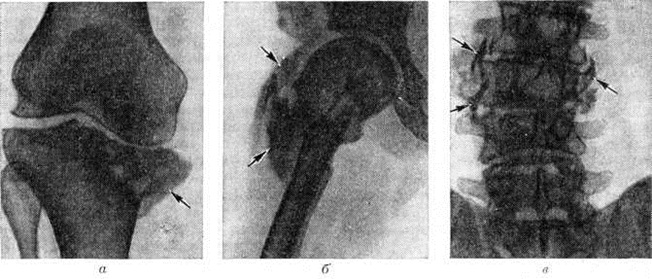

Патологическая анатомия. Макроскопически спинной мозг (смотри полный свод знаний) уплощен и истончен, его задние канатики и задние корешки спинномозговых нервов истончены и сморщены. Микроскопически в начальной стадии Спинная сухотка выявляют лептоменингит (смотри полный свод знаний: Менингит) вокруг интрадуральной части задних корешков и в области задних канатиков с инфильтрацией лимфоцитами и плазматическими клетками, а также пролиферативные изменения в стенках сосудов, соединительной ткани, в пери и эндоневрии задних корешков. Описанные выше изменения более отчетливы в нижних отделах спинного мозга — крестцовом и поясничном. В стадии выраженной Спинная сухотка поражение характеризуется дегенерацией центральных отростков клеток спинномозговых узлов, при этом сами узлы обычно мало изменены. Особенно значительные дегенеративные изменения отмечают в экстрадуральной части задних корешков и в зоне их вступления в спинной мозг, где они сдавливаются фиброзно-утолщенными оболочками и разросшейся краевой глией (смотри полный свод знаний: Нейроглия). Дегенеративные изменения (распад миелиновой оболочки и осевых цилиндров аксонов, образующих задние канатики) волокон корешков распространяются вверх по задним канатикам спинного мозга. В заключительной стадии процесса на месте атрофированных волокон задних корешков и канатиков разрастается фибриллярная глия pi соединительная ткань. В поясничном и крестцовом отделах спинного мозга распад миелина начинается в медиальной части задних канатиков. В грудных и шейных сегментах спинного мозга дегенерации подвергается вся область задних канатиков (рисунок 1). Её обнаруживают и в периферических отростках клеток спинномозговых узлов, входящих в состав образований периферической нервной системы (сплетений, нервов), а также в различных отделах высшая нервная система Во многих случаях выявляют дегенерацию волокон черепно-мозговых (черепных) нервов в их внутричерепном отрезке. На разных стадиях Спинная сухотка могут обнаруживаться инфильтративные, пролиферативные и рубцовые изменения в оболочках головного мозга, а также поражение сосудов мозговых оболочек.

Рис. 1. | ||

Рентгенологическая картина табетических изменений в скелете иногда напоминает другие патологический процессы в суставах, например, деформирующий остеоартроз, туберкулёзный артрит (смотри, полный свод знаний: Артриты, Артрозы) или остеогенную саркому (смотри полный свод знаний). Дифференциальный диагноз следует проводить и с другими неврогенными поражениями скелета — при сирингомиелии (смотри полный свод знаний), повреждениях спинного мозга и периферических нервов.

К основным рентгенологическое признакам табетических артропатий относят патологический внутрисуставные переломы (смотри полный свод знаний), которые обычно бывают многооскольчатыми. Иногда патологический переломам сопутствует массивный некроз суставных концов костей (рисунок 2, а). Распад костной ткани в суставных концах костей приводит к их взаимному смещению — к подвывиху и вывиху. Отторгнутые в результате патологический внутрисуставного перелома костные фрагменты нередко выявляются рентгенологически как внутрисуставные свободные тела. В результате длительного функционирования поражённого сустава в патологический условиях в нем может произойти своеобразная взаимная отшлифовка суставных поверхностей. При менее выраженной деструкции костной ткани выявляется лишь уплощение естественного рельефа суставных поверхностей костей.

Важное значение в диагностике табетической артропатии (смотри полный свод знаний) имеют отсутствие костного анкилоза (смотри полный свод знаний), патологический обызвествления и окостенения в суставной капсуле и в околосуставных тканях. Этот процесс метапластического костеобразования рентгенологически проявляется бесформенными «известковыми» тенями вокруг деформированного сустава. В метафизах трубчатой кости при значительном разрушении суставных её концов могут быть выявлены периостальные наложения. При Спинная сухотка, несмотря на значительные деструктивные изменения в костях, остеопороз (смотри полный свод знаний) обычно отсутствует; часто наблюдают выраженный остеосклероз (смотри полный свод знаний). Внесуставные патологический переломы при Спинная сухотка сопровождаются продуктивной реакцией с образованием большой костной мозоли (рисунок 2, б), причём эта реакция более выражена в диафизах трубчатых костей и при значительном смещении отломков. В некоторых случаях патологический перелом может не сопровождаться заметной периостальной реакцией. Преобладанием продуктивных изменений отличаются и поражения позвоночника (спондилопатии) при Спинная сухотка (рисунок 2, в).